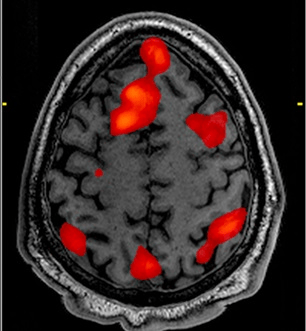

Foundational models for all modalities (MRI, PET, EEG, iEEG, MEG)

Foundational Models for (MRI, PET)